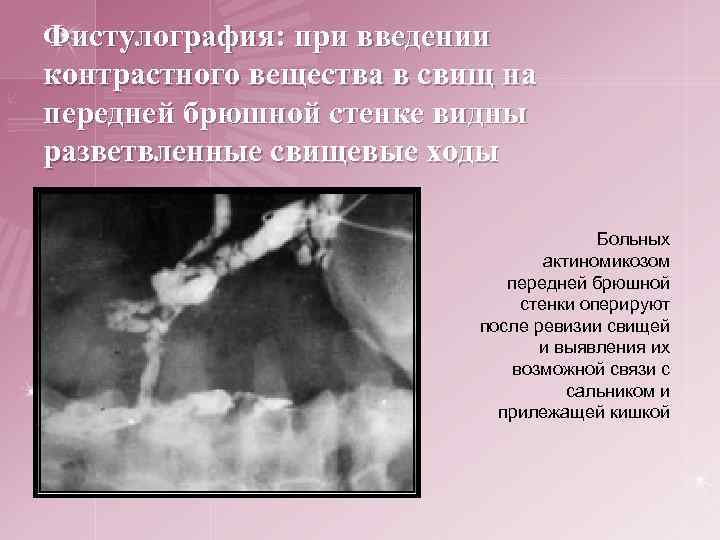

Фистулография: при введении контрастного вещества в свищ на передней брюшной стенке видны разветвленные свищевые ходы Больных актиномикозом передней брюшной стенки оперируют после ревизии свищей и выявления их возможной связи с сальником и прилежащей кишкой